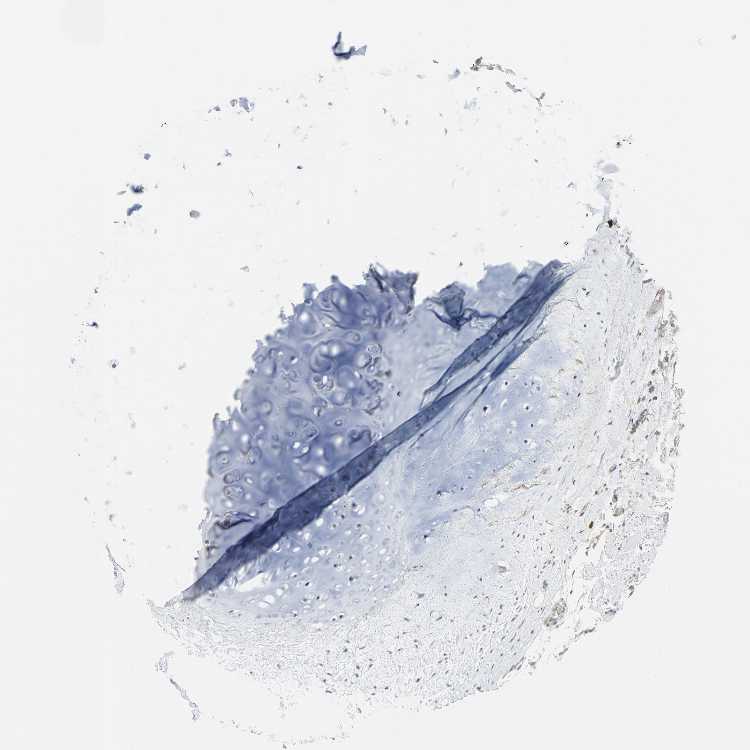

SOFT TISSUE 2 - Antibody stainingi

Antibody staining in the annotated cell types in the current human tissue is reported as not detected, low, medium, or high, based on conventional immunohistochemistry profiling in selected tissues. This score is based on the combination of the staining intensity and fraction of stained cells.

Each image is clickable and will lead to virtual microscopy that enables deeper exploration of all samples and also displays staining intensity scores, fraction scores and subcellular localization as well as patient and tissue information for each sample.

Antibody HPA004098

Fibroblasts Not detected

Peripheral nerve Not detected